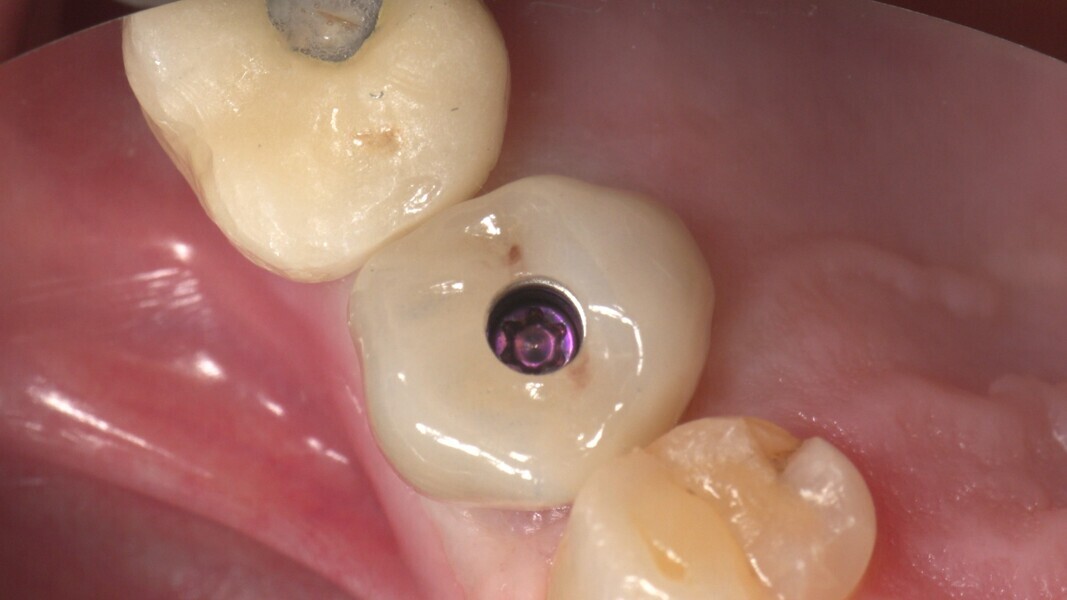

Conventional and immediate loading with final n!ce screw-retained crowns